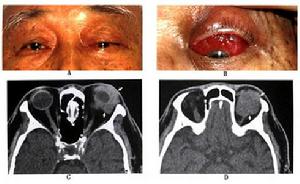

眼眶非霍奇金惡性淋巴腫瘤的分類雖然複雜臨床表現卻較為一致且多見於淚腺區,這是因正常淚腺內有淋巴組織存在的緣故一側或兩側眼瞼腫脹下垂,捫及無痛性硬性腫物眼球突出並向一側移位,球結膜水腫。因病變浸潤性增生,波及視神經和眼外肌,視力減退經常發生,眼球運動受限,甚者眼球固定結膜下侵犯可透過結膜看到粉色魚肉樣腫物惡性程度較高的腫瘤發展較快,眼瞼浸潤變硬遮住眼球,與眶內腫物連為一體。腫瘤發生的年齡和臨床表現與淋巴浸潤炎性假瘤頗為相似尤其是需要與淚腺炎型假瘤進行鑑別診斷眶內惡性淋巴瘤有時伴有其他部位淋巴結腫大需全身詳細檢查。

根據病史及臨床表現,並結合影像學檢查,診斷並不難最後確診還要靠活體組織檢查

鑑別診斷: 主要是和淚腺上皮性腫瘤鑑別後者為多回聲或中高反射。但和淚腺炎性假瘤區別困難必要時活檢證實診斷。最易和其混淆的是淋巴細胞性炎性假瘤,兩者在臨床和影像上均類似僅淋巴瘤年齡偏大最後鑑別需要病理證實。